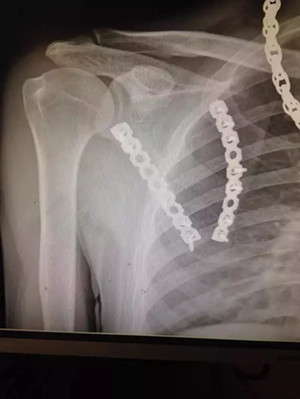

患者小陳(化名)因車禍致肩部受傷到廣安醫(yī)院就診,被診斷為“左側肩胛骨粉碎性骨折”,骨折端分離移位明顯。

術后拍片